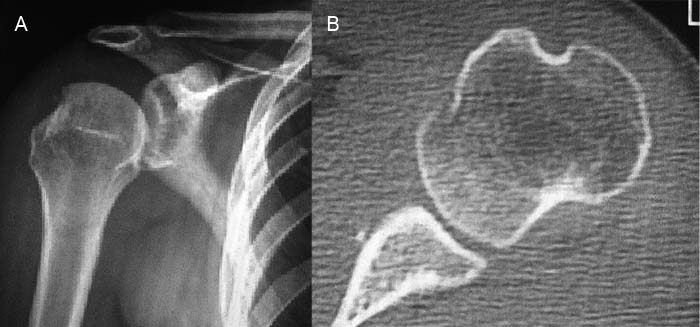

La resonancia magnética (RM) por su parte, permite evaluar ligamentos, tendones del manguito rotador y la lesión de Hill-Sachs, lo cual es de suma importancia a la hora de decidir el adecuado tratamiento (Fig. 1).

Figura 1: A: Radiografía en proyección AP con rotación interna. Se observa defecto Hill Sach. B: TAC de hombro, efecto posterolateral de la cabeza humeral .